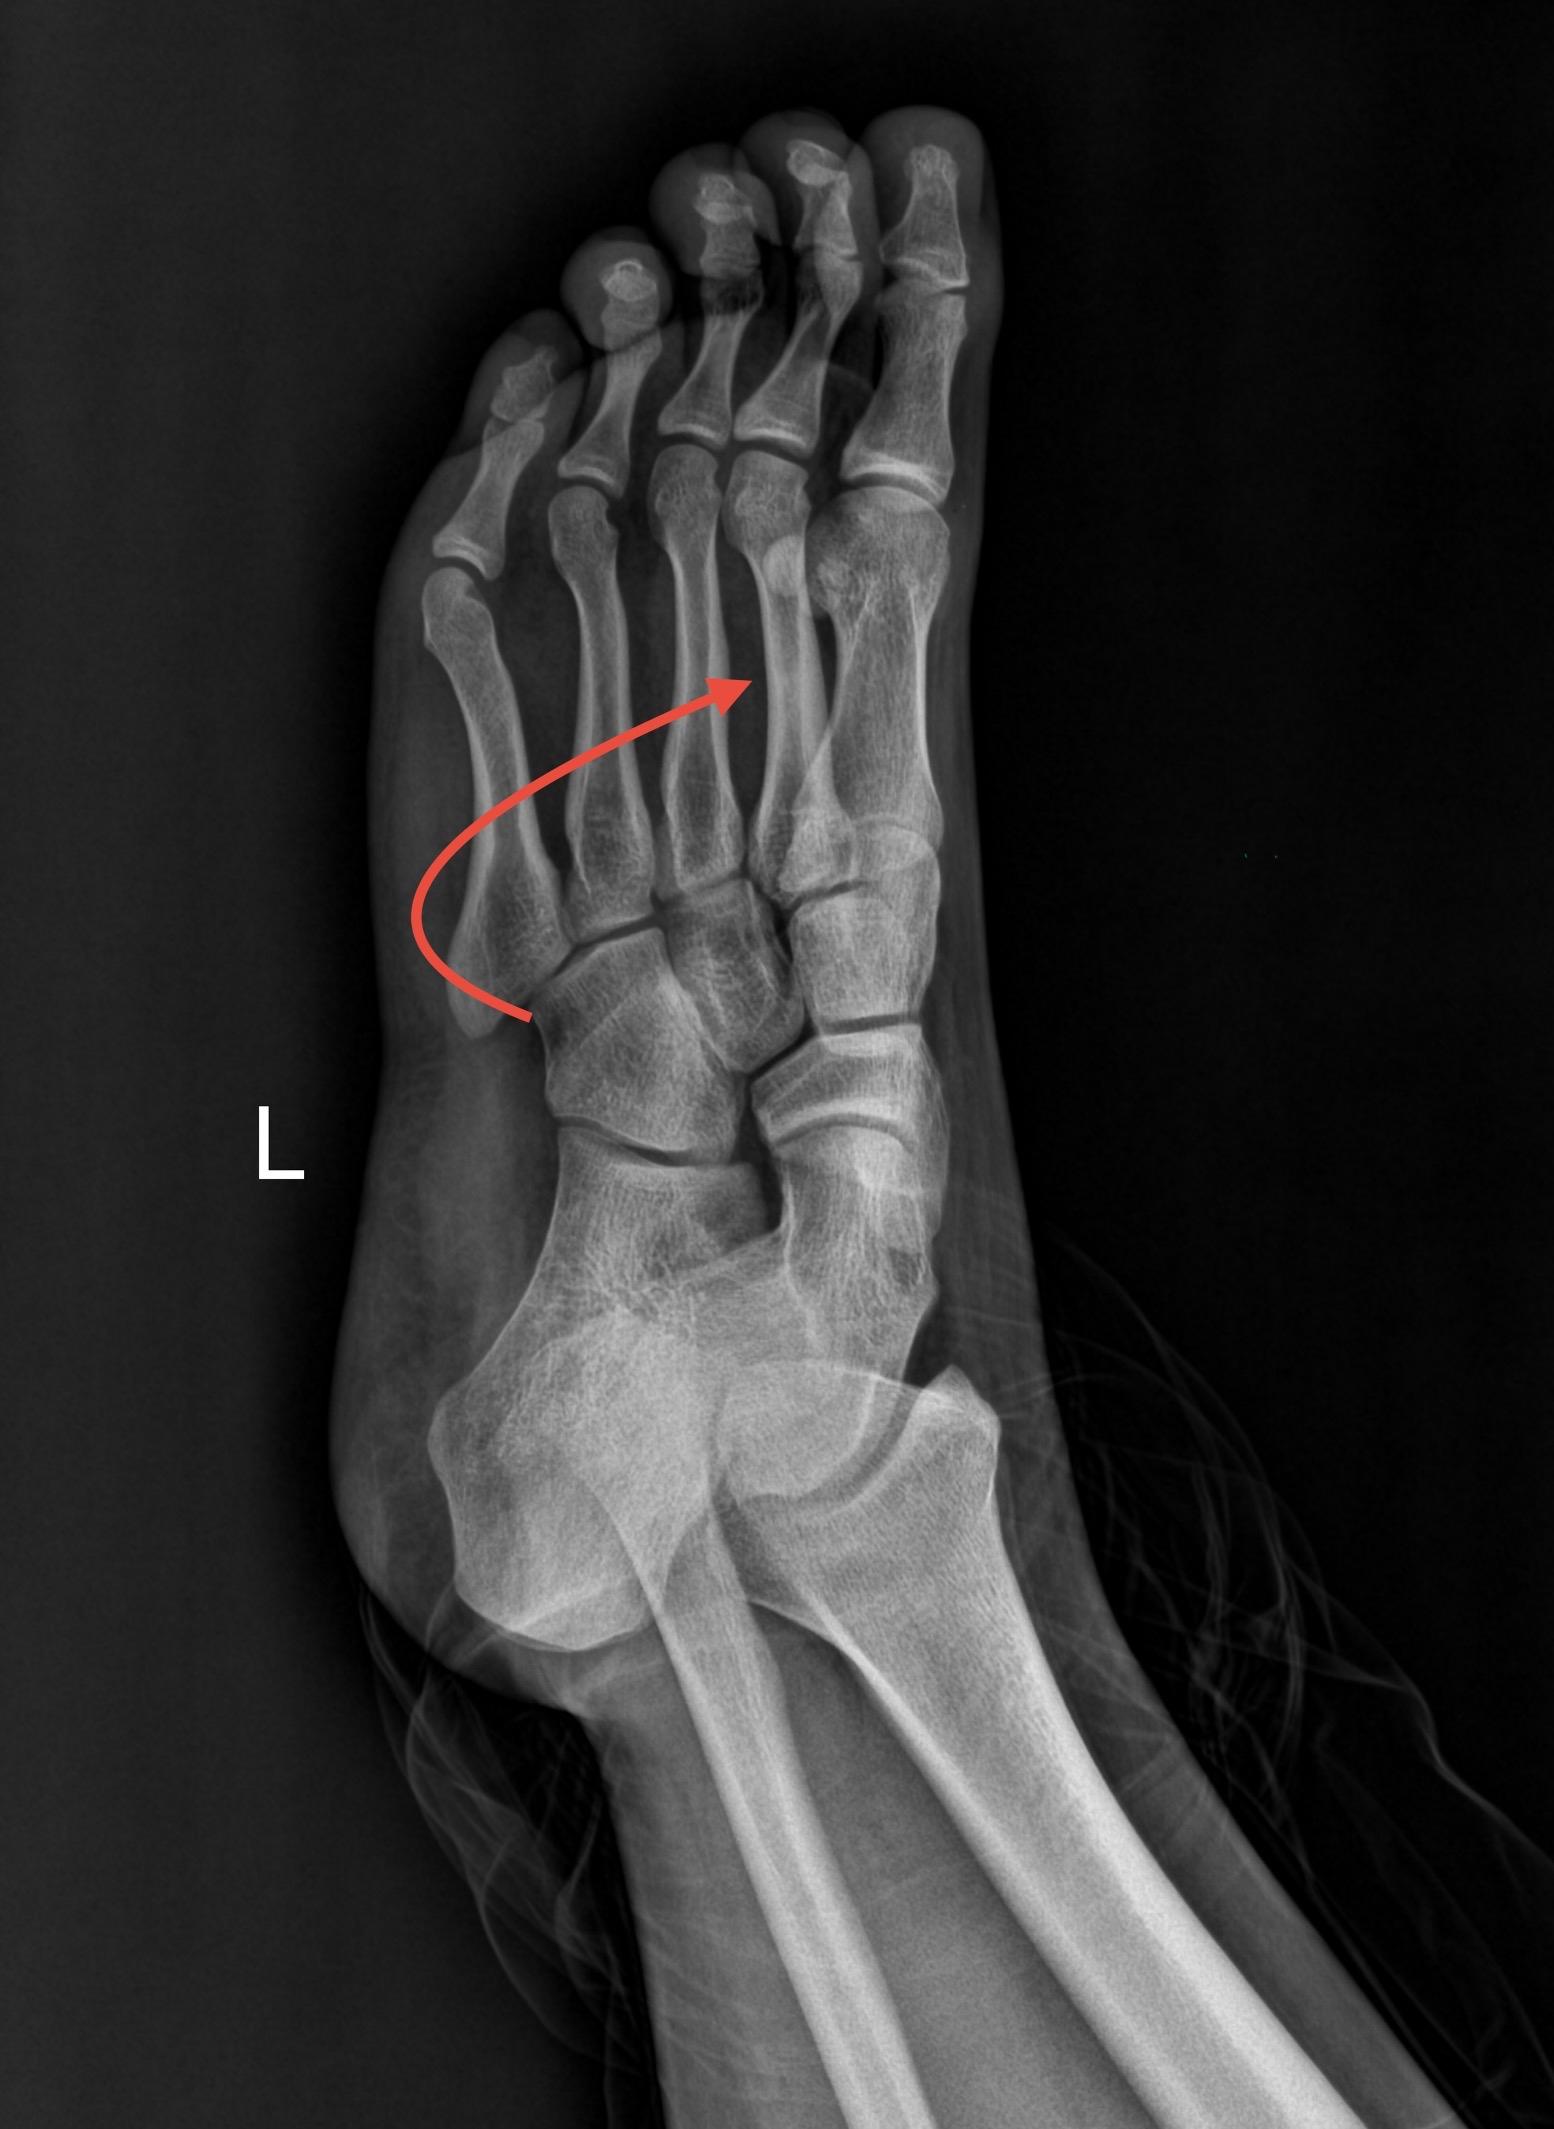

【骨肌】爱运动的烦恼!男,15岁,双侧足底部隐痛,爱好运动,喜欢长跑与打羽毛球!

男,15岁,双侧足底部隐痛,爱好运动,喜欢长跑与打羽毛球!